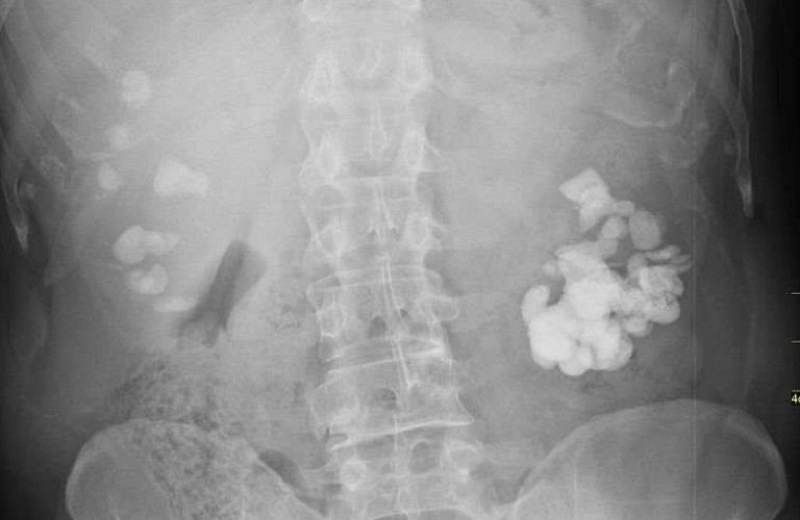

2.2. Chẩn đoán hình ảnh sỏi thận bằng chụp X-quang

Chụp X-quang là phương pháp chẩn đoán hình ảnh sử dụng tia X có khả năng xuyên thấu qua các mô mềm của cơ thể. Tuy nhiên, tia X sẽ bị cản lại khi gặp các mô cứng như xương, răng hoặc các chất cản quang, tạo ra hình ảnh có sự khác biệt về độ sáng – tối tùy theo mức độ hấp thụ tia X tại từng vị trí trong cơ thể.

Hiện nay, có hai loại chụp Xquang hệ niệu phổ biến là chụp Xquang không chuẩn bị và chụp Xquang có tiêm thuốc cản quang. Cả hai phương pháp này đều yêu cầu bệnh nhân được chuẩn bị trước bằng cách thụt tháo hoặc sử dụng thuốc nhuận tràng để loại bỏ hơi và phân trong đại tràng, giúp tăng độ rõ nét của hình ảnh.

Điểm khác biệt chính giữa hai kỹ thuật này là việc sử dụng chất cản quang:

– X-quang không chuẩn bị không cần dùng chất cản quang, chủ yếu để phát hiện sỏi có cản tia.

– X-quang có tiêm thuốc cản quang giúp đánh giá rõ hơn cấu trúc và chức năng của đường tiết niệu, hỗ trợ phát hiện các bất thường không thể thấy trên X-quang thường.

Phương pháp này đóng vai trò quan trọng trong chẩn đoán sỏi thận, nhưng trong nhiều trường hợp, bác sĩ có thể kết hợp thêm các kỹ thuật hình ảnh khác như siêu âm hoặc chụp CT để có kết quả chính xác hơn.